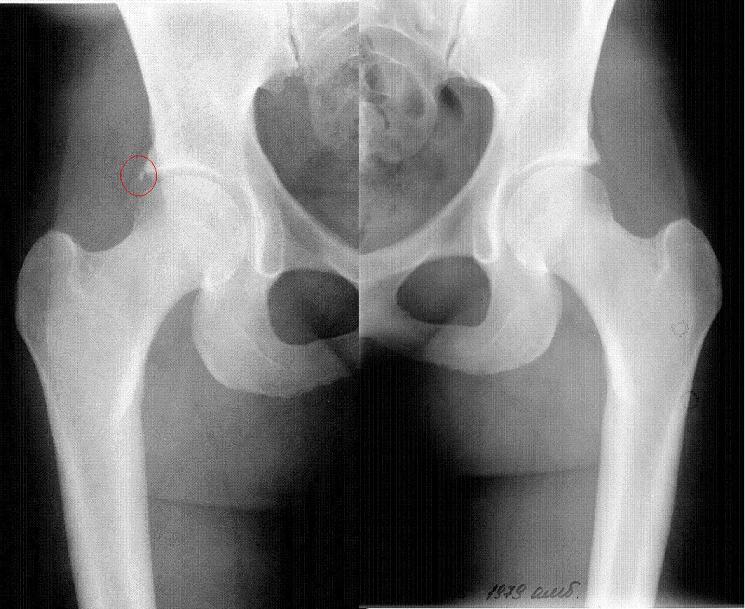

Рентгеновские снимки: Синовит тазобедренного сустава